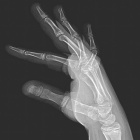

12 year old presents with lump over right 5th digit, has a history of acute lymphocytic leukemia that is in remission for seven years, status post bone marrow transplant after whole body irradiation

Zoom image: Radiological image Radiological image.